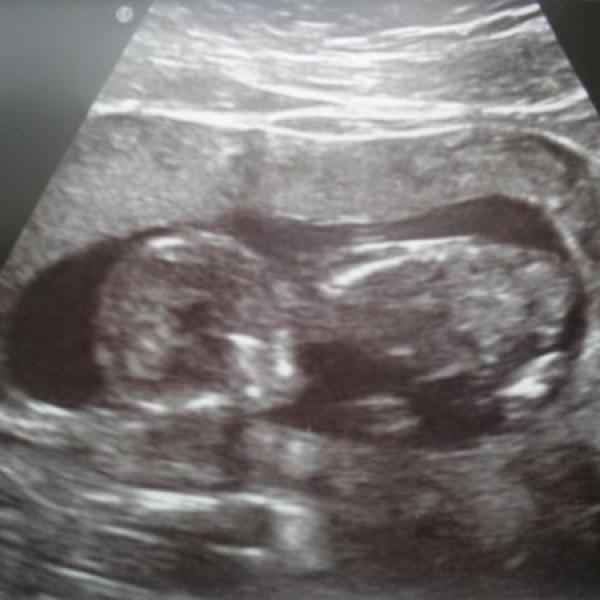

Ahoj, tak jsem dnes byla na prvostrimestrálním screeningu, a naštěstí všechno dopadlo dobře. Prcek už měří 7 cm a odpovídá dle utz i dle ms 13+0tt.